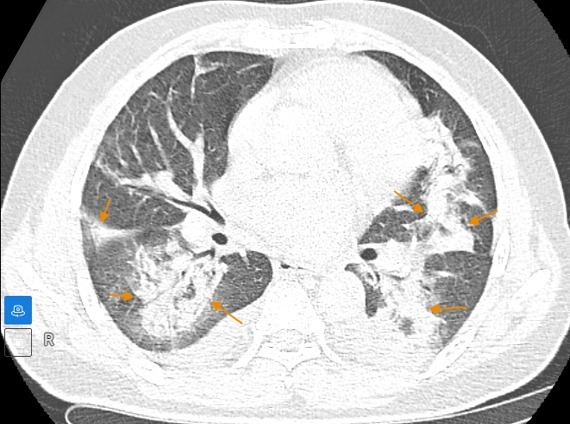

Hình ảnh chụp CT phổi độ phân giải cao cho thấy tổn thương đông đặc nhu mô phổi kèm xẹp phổi quanh bó mạch, phế quản, dày tổ chức kẽ dạng lưới, các vùng kính mờ lan tỏa trong nhu mô phổi và tràn dịch khoang màng phổi hai bên.

Từ các dữ liệu lâm sàng và hình ảnh học, bệnh nhân được chẩn đoán xác định mắc viêm phổi tổ chức hóa (Cryptogenic Organizing Pneumonia - COP), một dạng viêm phổi hiếm gặp.